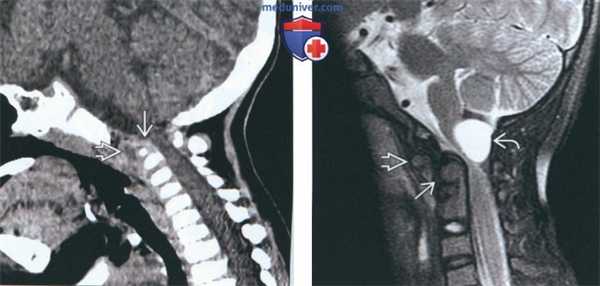

(Слева) На сагиттальной МРТ (Т2 ВИ) в положении сгибания определяется переднее положение дистопической зубовидной костив относительно С2. Расстояние между передней дугой С1 и зубовидной костью сохранено; определяется нарушение положения зубовидной кош относительно С2 по сравнению с изображениями в нейтральном положении и при разгибании (атланто-аксиальная нестабильность).

(Справа) На сагиттальной MPT (Т2 ВИ) в положении разгибания у этого же пациента положение зубовидной кости обычное. На сагиттальной МРТ (Т2 ВИ) в положении сгибания определялось переднее смещение зубовидной кости, свидетельствующее об атланто-аксиальной нестабильности.